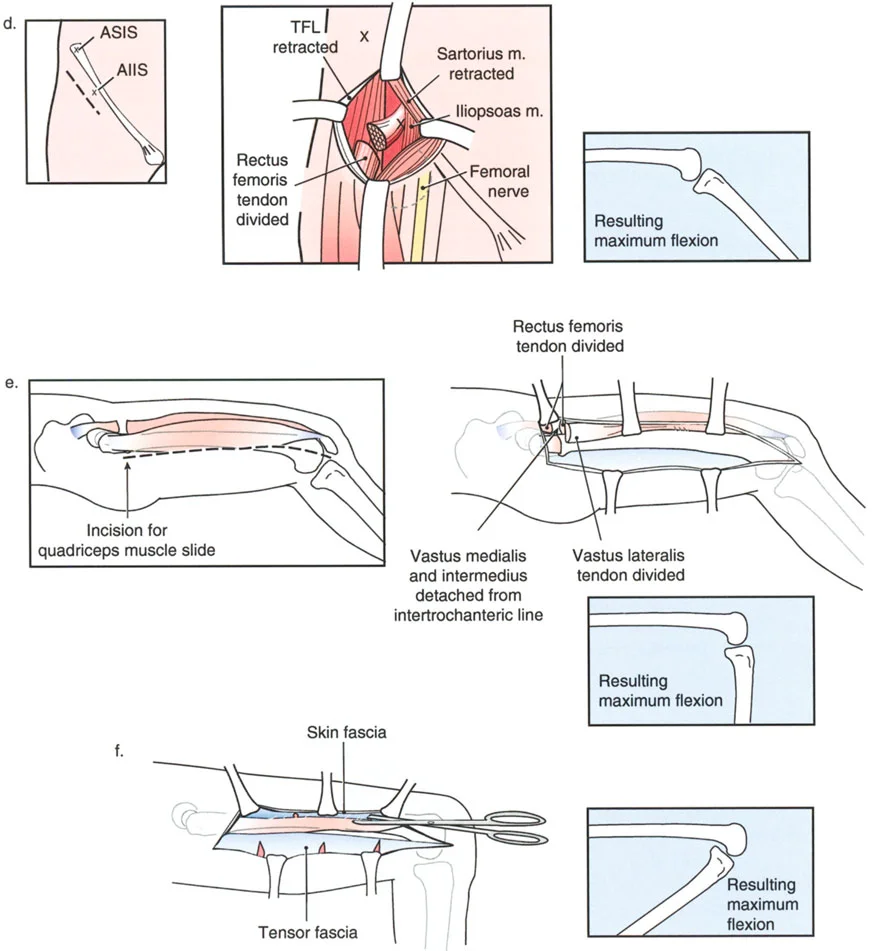

دور الحدبة الظنبوبية في التخطيط لقطع العظم

عند التخطيط لقطع العظم لتصحيح التقوس الخلفي في الظنبوب، فإن موقع القطع العظمي بالنسبة للحدبة الظنبوبية هو القرار الأكثر أهمية الذي سيتخذه الجراح. فالنتائج الميكانيكية الحيوية لهذا الاختيار تحدد ما إذا كان خلع الركبة الجزئي سيتم تقليله أو تفاقمه بشكل كارثي.

قطع العظم فوق الحدبة الظنبوبية (النهج المفضل)

عندما يوجد تشوه تقوس خلفي مع وجود الحدبة الظنبوبية بالقرب من خط المفصل، فإن قطع العظم على شكل إسفين فتح فوق الحدبة الظنبوبية يكون مفيداً للغاية ويمثل المعيار الذهبي في مبادئ بالي لإعادة البناء.

- آلية العمل: يؤدي فتح إسفين عند هذا المستوى المحدد إلى تصحيح محاذاة العظم التقوسية، واستعادة زاوية PPTA الطبيعية (81-84 درجة) مباشرة.

- تقليل المفصل غير المباشر: نظراً لأن الحدبة الظنبوبية تبقى على الجزء البعيد من قطع العظم، فإن فتح الإسفين للأمام يسحب وتر الرضفة جسدياً. يعمل هذا الشد كحزام تقليل داخلي، يسحب كامل ساق الظنبوب وهضبة الظنبوب للأمام، وبالتالي يقلل بشكل غير مباشر الخلع الجزئي الخلفي للمفصل الظنبوبي الفخذي.

- منع انخفاض الرضفة: قد يفترض المرء أن سحب الحدبة الظنبوبية للأسفل سيسبب انخفاضاً في الرضفة. ومع ذلك، نظراً لأن كامل الظنبوب يتحرك للأمام وتتغير زاوية المفصل، فإن انخفاض الرضفة الثانوي لا يحدث. يتم الحفاظ على المسافة النسبية بين الرضفة وخط المفصل.

- نقل الشظية: يمكن أن يساعد نقل الشظية للأسفل أيضاً في تقليل الخلع الجزئي الخلفي. نظراً لأن الرباط الجانبي الوحشي (LCL) موجه في اتجاه أمامي خلفي، فإن سحب الشظية للأسفل يشد الرباط الجانبي الوحشي، مما يساعد في الترجمة الأمامية للظنبوب.

مخاطر قطع العظم تحت الحدبة الظنبوبية

على العكس من ذلك، إذا تم إجراء قطع عظمي على شكل إسفين فتح أسفل الحدبة الظنبوبية، فإن الجراح يخلق كارثة ميكانيكية حيوية.

بينما قد يتم تصحيح التقوس الخلفي في ساق الظنبوب إشعاعياً، فإن الخلع الجزئي الخلفي للمفصل يترك دون علاج تماماً. نظراً لأن الحدبة الظنبوبية تقع على الجزء القريب، فإن وتر الرضفة لا يتم شده. يبقى المفصل مخلوعاً جزئياً، مما يؤدي إلى عدم استقرار مستمر، وتآكل سريع للغضروف، وآلام غير محلولة.